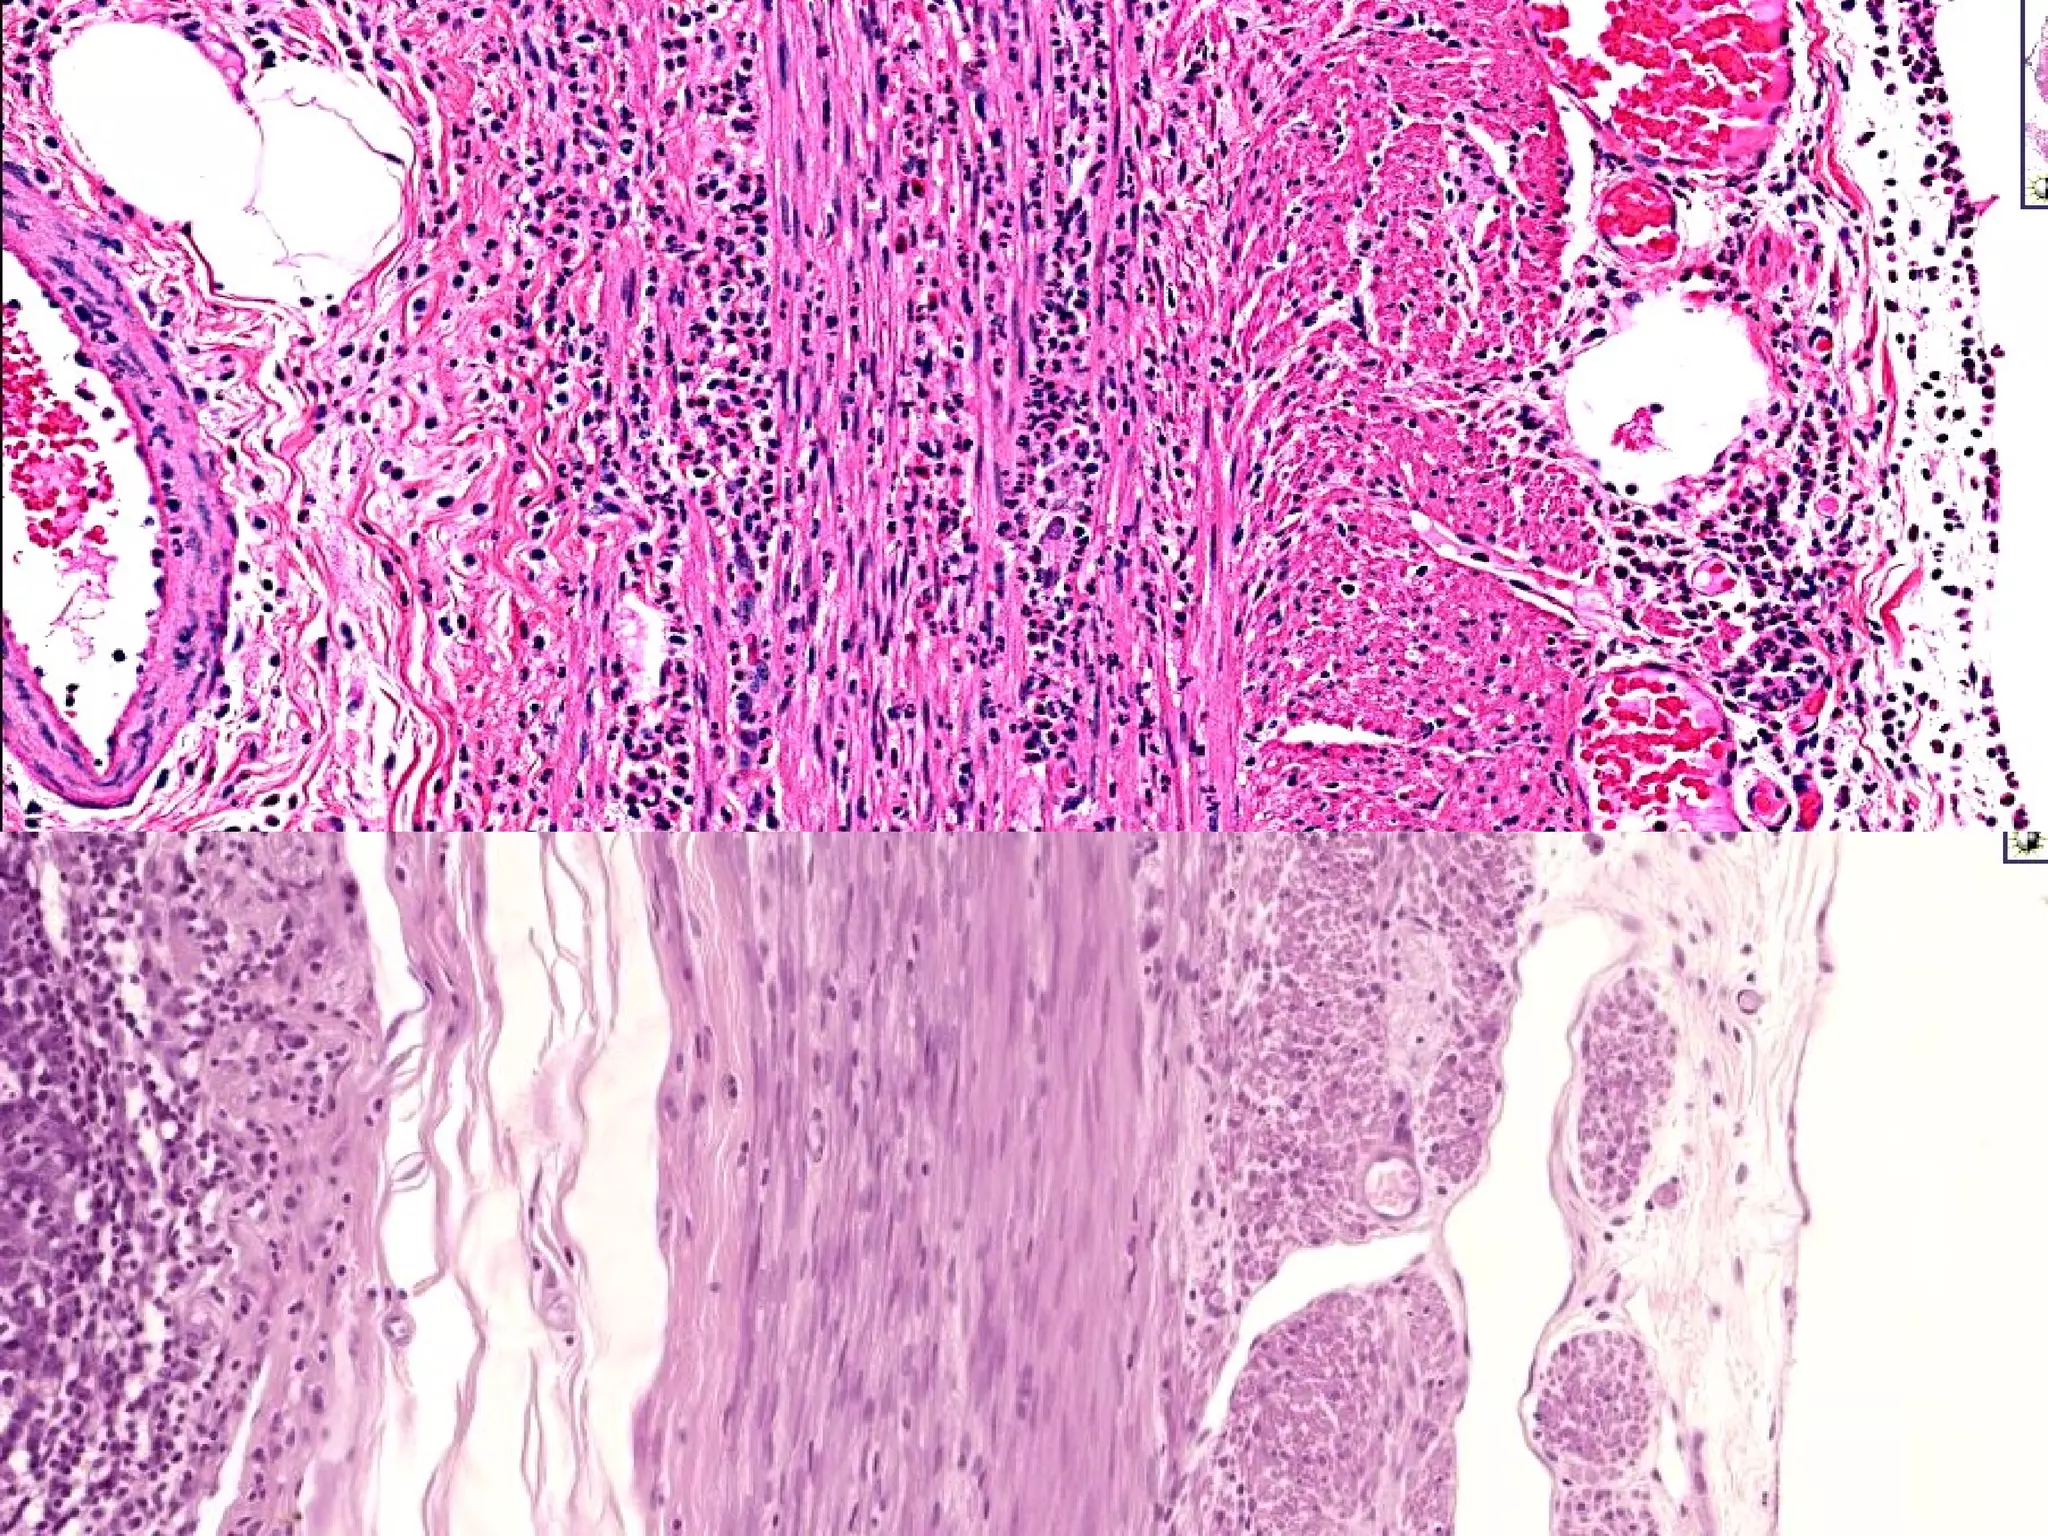

REFLUX/GERD Inflammatory Cells Eosinophils Neutrophils Lymphocytes Basal zone hyperplasia Lamina Propria papillae elongated and congested www.freelivedoctor.com

BARRETT’S ESOPHAGUS Can be defined as intestinal metaplasia of a normally SQUAMOUS esophageal mucosa.  The presence of GOBLET CELLS in the esophageal mucosa is DIAGNOSTIC. SINGLE most common RISK FACTOR for esophageal adenocarcinoma 10% of GERD patients get it “ BREACHED” G-E junction

BARRETT’S ESOPHAGUS INTESTINALIZED (GASTRICIZED) mucosa is AT RISK for glandular dysplasia. Searching for dysplasia when BARRETT’s is present is of utmost importance MOST/ALL adenocarcinomas arising in the esophagus arise from previously existing BARRETT’s

• #18 Note that the image on the right is the NON-microscopic demonstration of a squamo-columnar junction.

• #26 You can think of Barrett’s as REVERSE squamous metaplasia.

• #28 Barrett’s on top, goblet cell on right, normal esophagus on bottom.